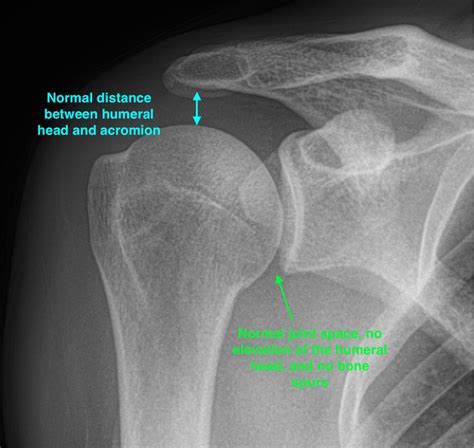

Interpreting X Ray Shoulder Joint results requires a trained eye. Radiologists look for specific signs and abnormalities that indicate various conditions. Some key points to consider include:

• Bone Density: Changes in bone density can indicate conditions like osteoporosis or bone tumors.

• Fractures: Visible breaks or cracks in the bones.

• Joint Space: The space between the bones can indicate the presence of arthritis or other degenerative conditions.

• Soft Tissue: Although X-rays primarily show bones, they can also reveal certain soft tissue abnormalities.

Radiologists use these findings to make a diagnosis and recommend appropriate treatment options.